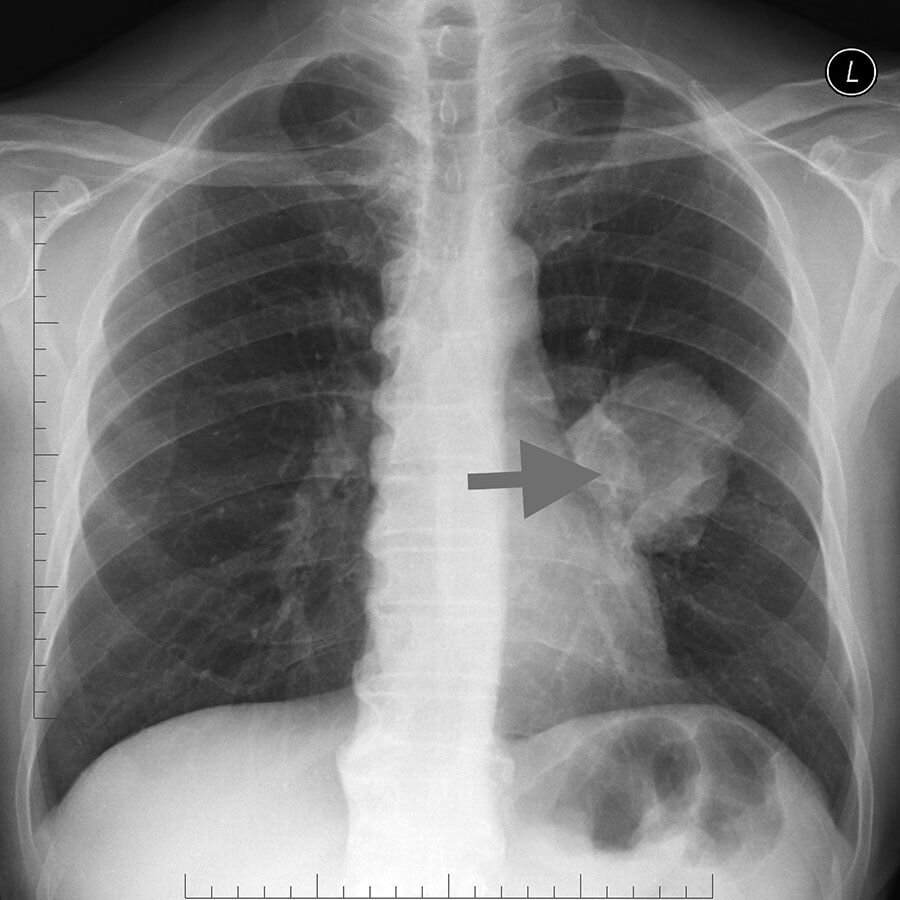

Туберкулез. Снимок из сети.

Начну рассказ с того как выявили туберкулез.При прохождении ежегодного мед осмотра, у меня обнаружили ТУБЕРКУЛЕЗ!!! Точнее говоря у меня на снимки обнаружили пятна, ну а потом поставили диагноз.